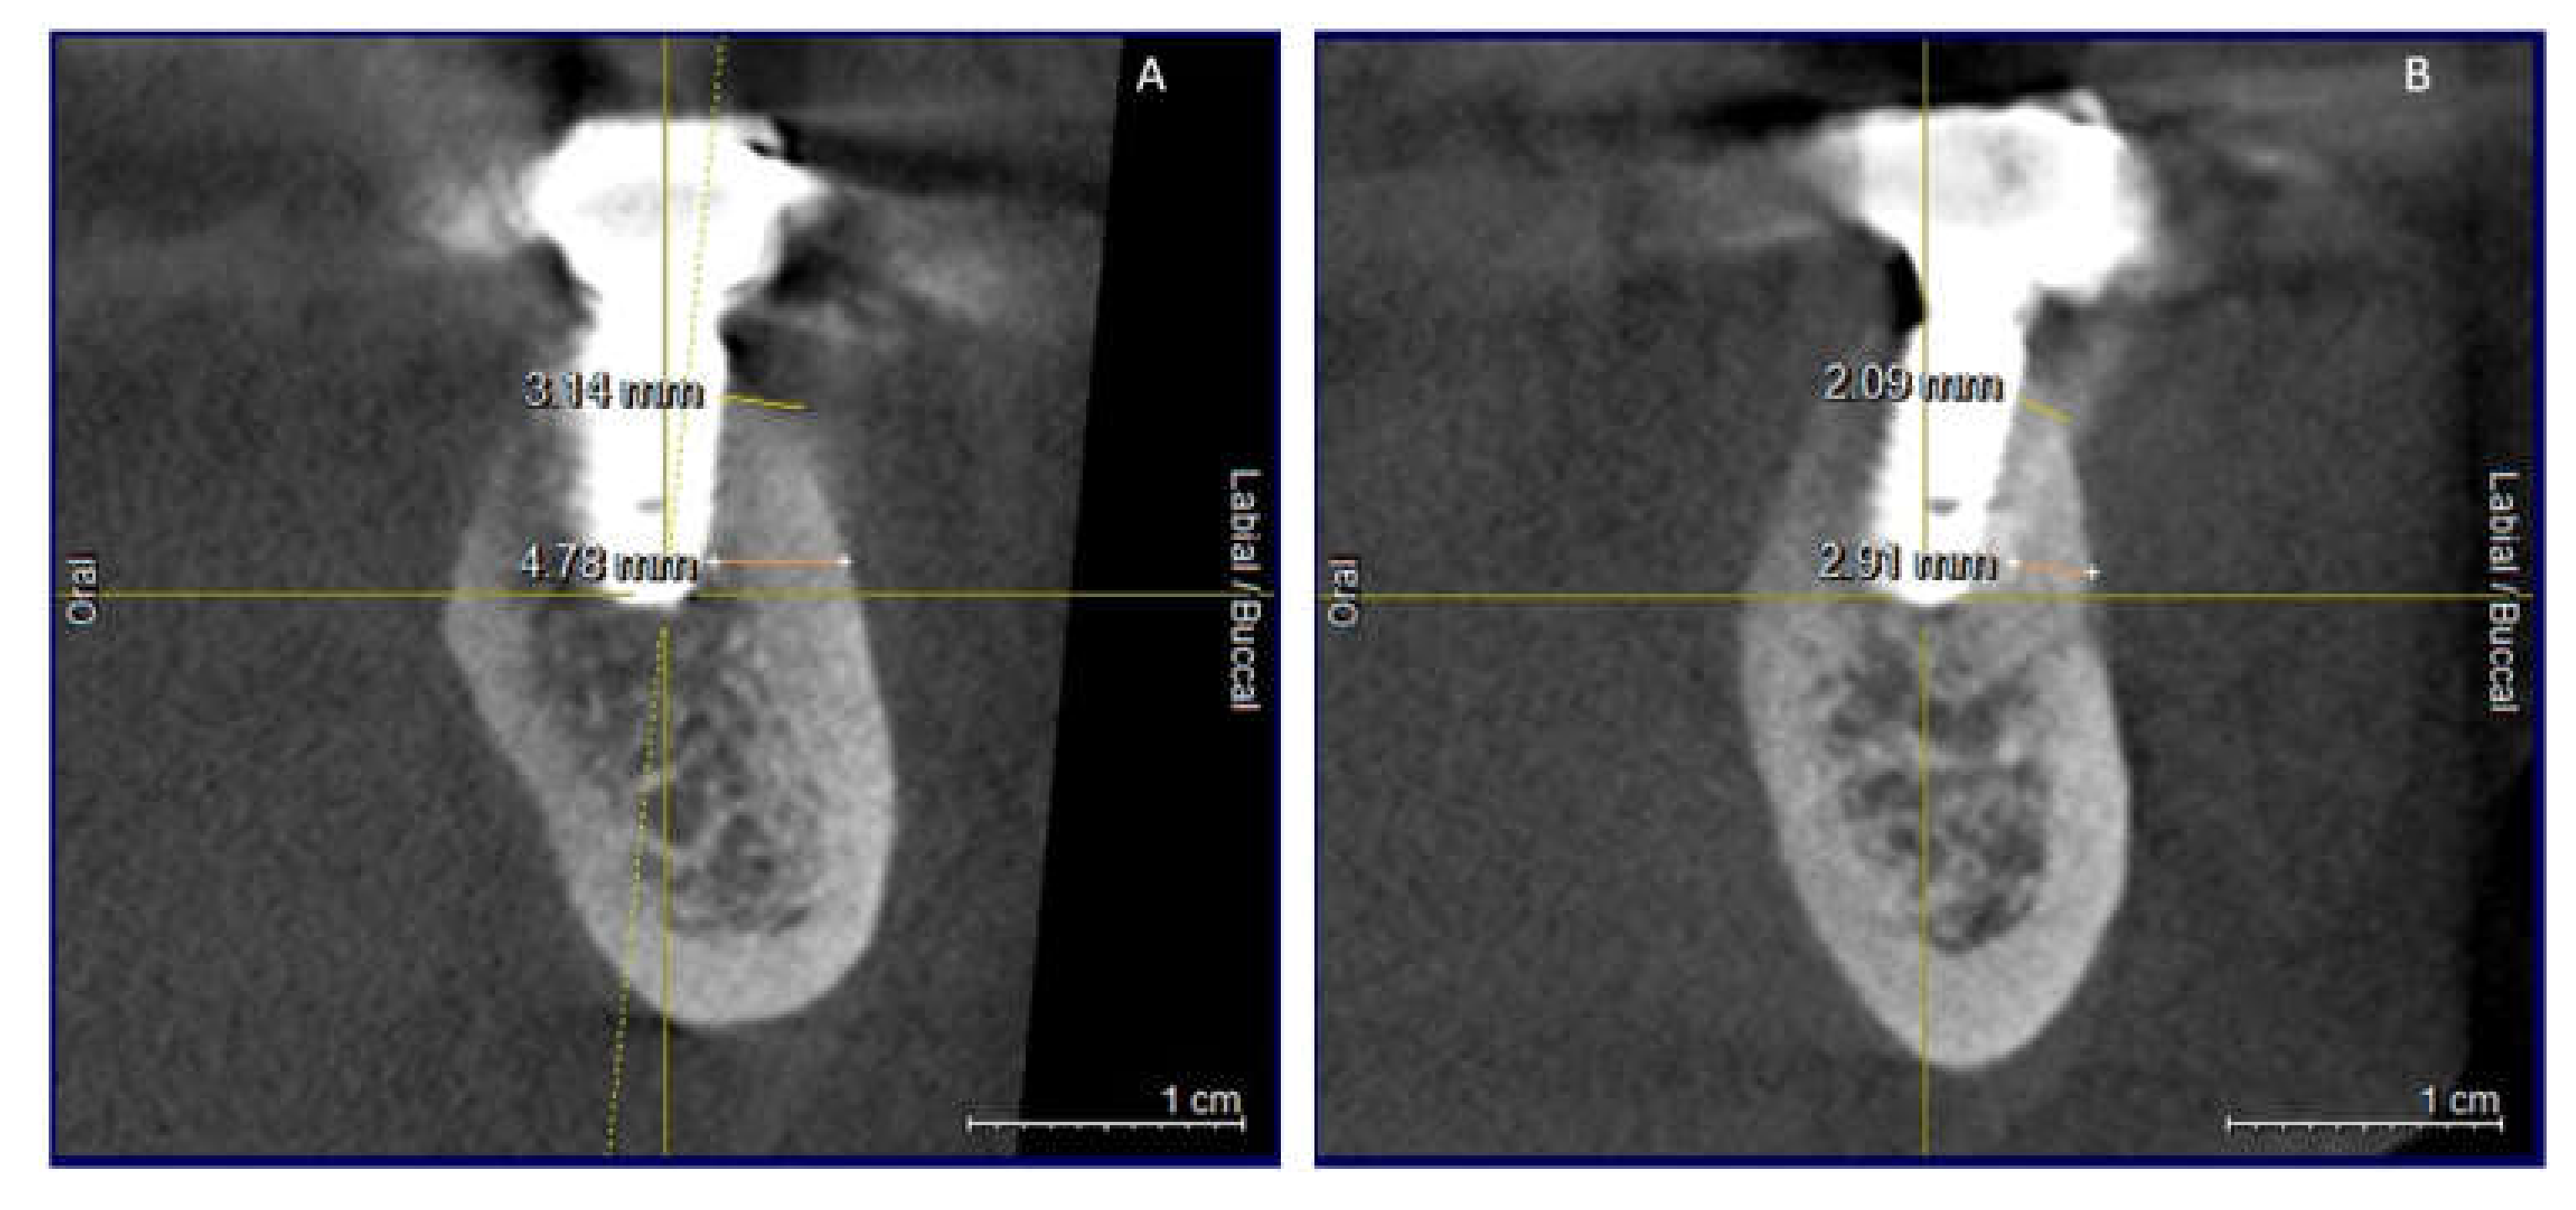

Clinical and CBCT aspects of patient from the test group, describing the stages of S-GBR technique and implant-prosthetic stage, are presented in Figure 1, Figure 2, Figure 3, Figure 4, Figure 5, Figure 6, Figure 7, Figure 8, Figure 9, Figure 10 and Figure 11. CBCT exam allows the evaluation of the horizontal alveolar bone defect and the position of the mandibular alveolar nerf (Figure 1A,B). Figure 1C,D show cross-sectional CBCT aspects of the implant sites. Figure 2 shows the narrowed mandibular alveolar bone with horizontal resorption. Figure 3 shows the exposed buccal surface of the alveolar ridge with severe horizontal resorption, after flap opening. The inserted implants (4.5 mm diameter, 11.5 mm length) and osteosynthesis screws (45° from the occlusal plan) are shown in Figure 4A. The placement of graft (autologous bone and xenograft) and collagen membrane is shown in Figure 4B. Figure 5A shows tension-free sutures, due to periosteal incisions alveolar ridge. Figure 5B shows clinical aspect at 7 months after surgery, with gingival tissue adherent on the reconstructed alveolar ridge. Figure 6 shows OPG aspect at follow-up of 7 months, with osseointegration of the dental implants. Figure 7A shows clinical aspect before osteosynthesis screws removal. Figure 7B shows clinical aspect after osteosynthesis screws removal. Figure 8A shows healthy peri-implant soft tissues. Figure 8B shows repositioning key for perfect position of abutments. Figure 10A,B show clinical aspects of implant-supported prosthetic restoration. Figure 11A,B show CBCT aspects of Osseo integrated dental implants at 24 months follow-up.

Figure 7.

(A,B) 7-months follow-up of S-GBR surgery. (A) CBCT shows 2 mm bone around implants. (B) CBCT shows reduced bone resorption in the coronal area of implants.

Figure 11.

(A,B) CBCT aspects (cross-sectional) of osseointegrated implants at 24-months follow-up.